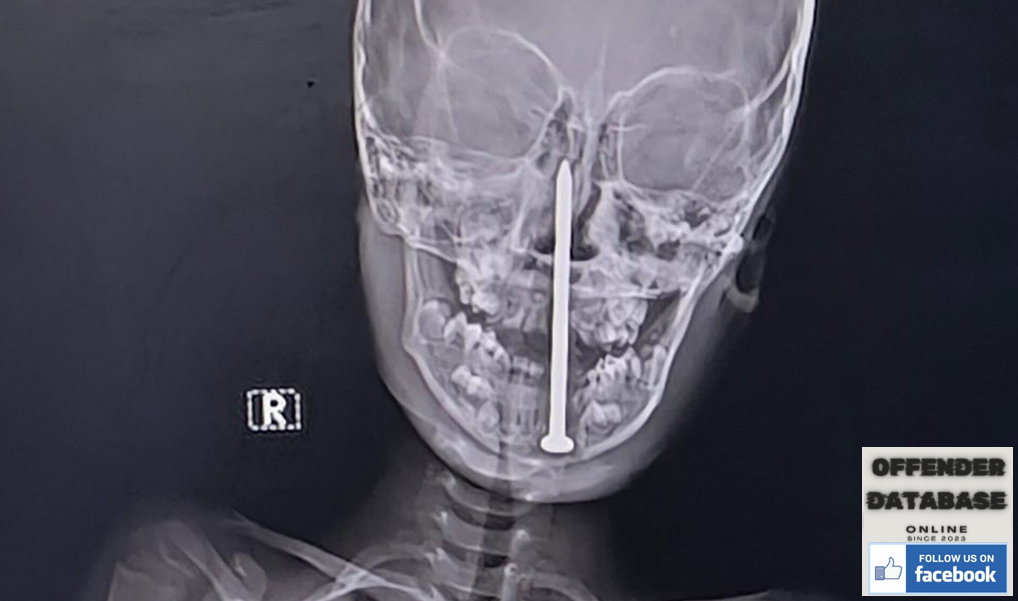

A child molester has been charged with hammering an 8cm iron nail into a girl’s skull in an effort to quiet her. A seven-year-old was assaulted by an unidentified male who subsequently drove a nail through her mouth, entering her palate and brain, as reported by her mother to medics in India.

Dr Samir Misra, a surgeon at KGMU, told The Telegraph that the nail had entered through the girl’s lower jaw and neck before reaching her cranial cavity, narrowly missing major arteries.

“This was an extraordinarily complex case where the child’s life was in serious jeopardy,” said Dr Misra. “It took us four hours to remove the nail that was touching the brain and it was dangerously close to vital blood vessels.

“Our team worked meticulously to avoid any damage to the brain and sensitive nerves between the mouth and the brain,” the doctor added.

In the early hours of May 16, the patient was referred to KGMU, where a specialist team conducted examinations including CT scans. Clinical evaluation and imaging revealed the nail’s path through several high-risk anatomical zones.